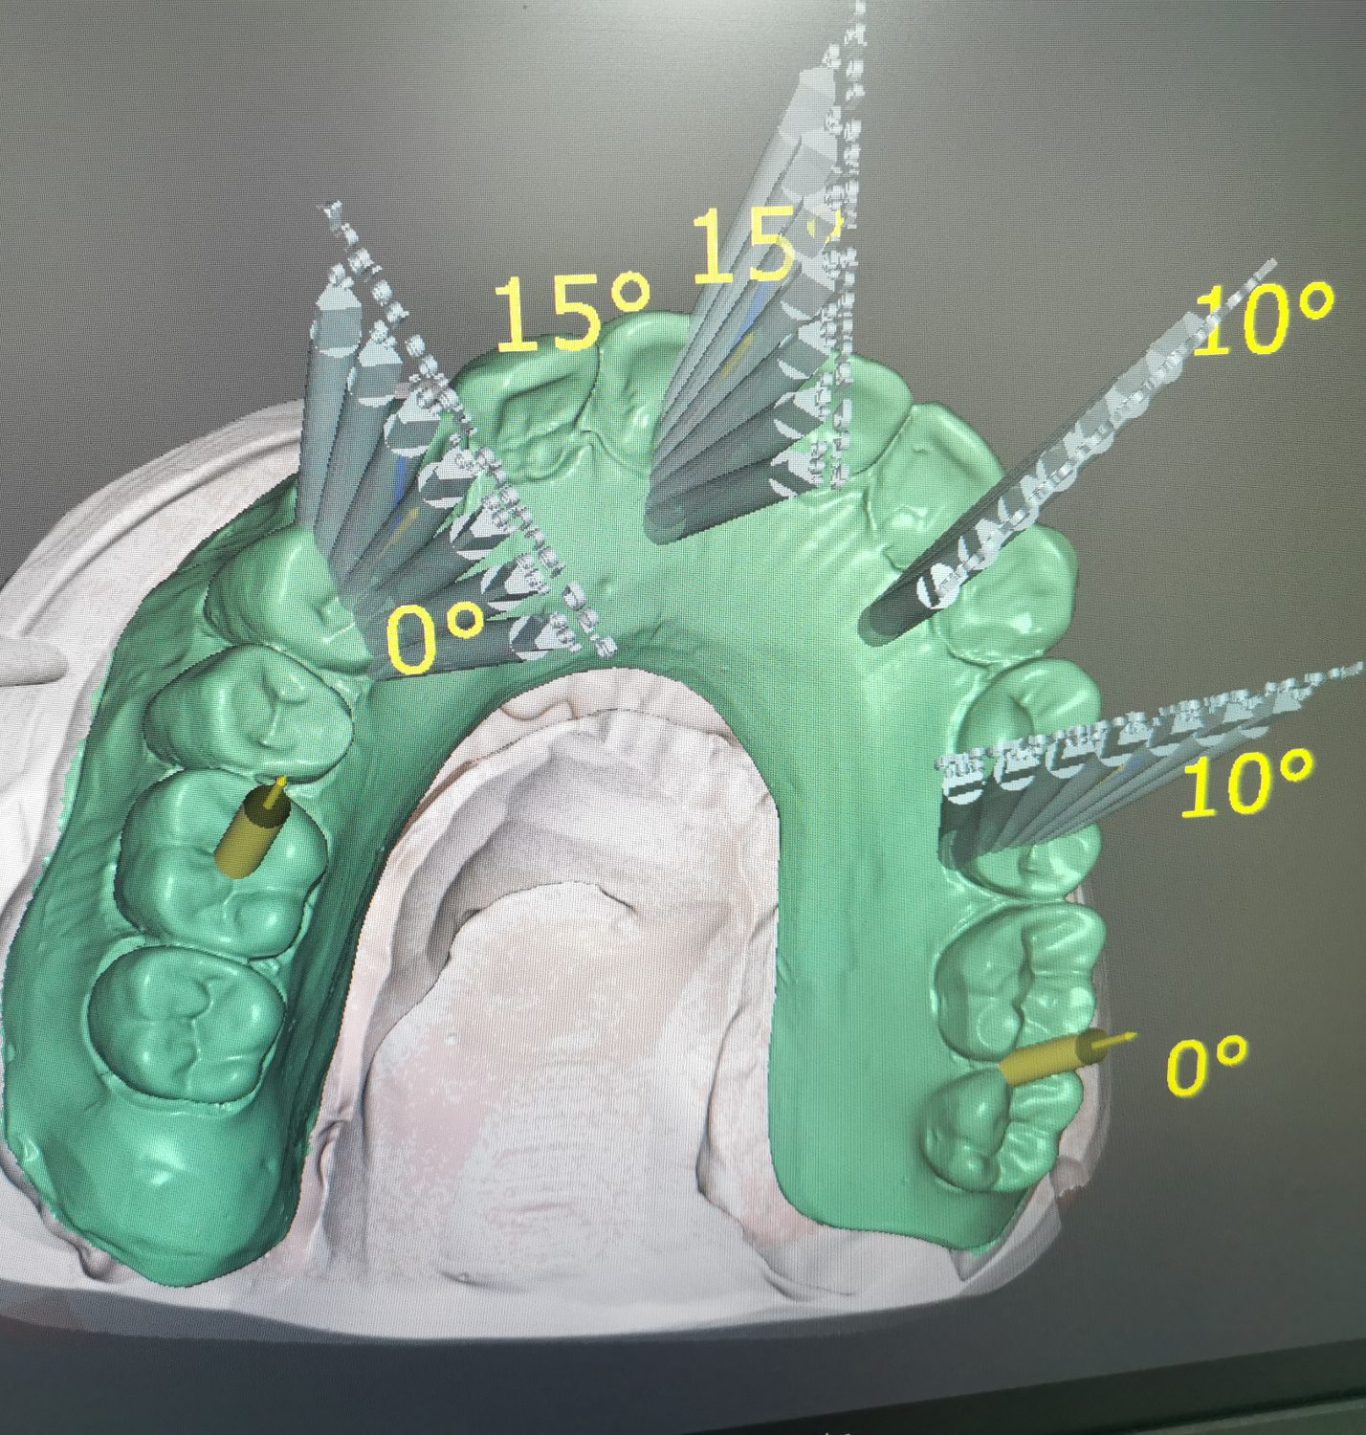

Moderne Technologie

Innovative CAD/CAM-Verfahren gewährleisten Präzision und optimale Passgenauigkeit.